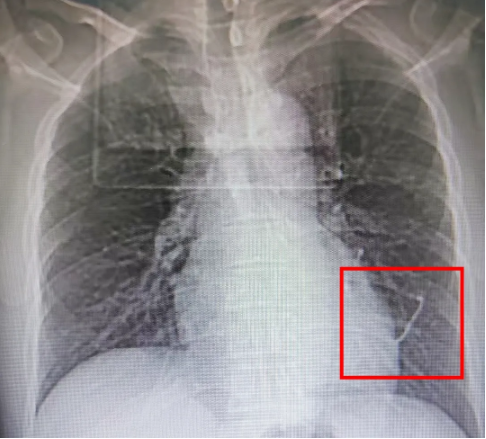

段先生是一名工业零部件加工从业者,在操作时被高速弹飞的异物刺伤左侧胸前区,随即出现剧烈胸痛、胸闷症状。同事第一时间呼叫120,将他送往附近医疗机构急救,肋骨DR检查提示“3-4肋间区域斑片状致密影”,高度怀疑金属异物刺入肺部。为求进一步救治,段先生被紧急转至市二医院急诊。

市二医院急诊科迅速响应,同步联系普、胸外科医师会诊。胸部CT检查结果跟怀疑情况基本重合:左肺下叶被金属异物完全穿透,伴周围肺挫伤,左侧胸腔积血、积气形成创伤性液气胸,3厘米长的异物嵌在肺内且紧邻心脏——一旦异物移位划伤心脏或肺组织持续出血,随时可能引发呼吸衰竭、失血性休克,情况十分危急,手术必须争分夺秒!